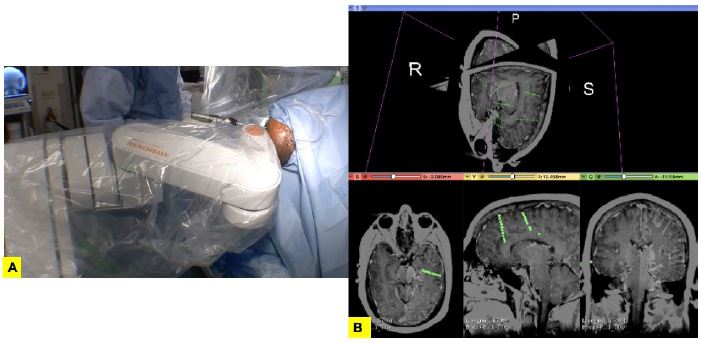

Robots en implantación de SEEG: existen varias plataformas, entre ellas, ROSA (Asistente Estereotáctico Robótico) (ZimmerBiomet/MedTech) y Neuro|MateTMRobot. (Renishaw/Reino Unido). Fueron diseñadas para SEEG y consisten en un brazo de 6 grados de movilidad y ángulos con base fija al piso. Se inserta directamente al ensamble que va al cráneo. Se realiza un co-registro de la IRM y tomografía del PCE (59) (figura 1).

Los electrodos pueden colocarse en sentido ortogonal u oblicuos. Son útiles en casos de difícil acceso (la ínsula, escondida debajo del opérculo temporal y frontoparietal, sin mencionar el riesgo de compromiso vascular al insertar los electrodos) (60).

A. Robot Neuro|MateTM(Renishaw plc) en la sala quirúrgica asistiendo al neurocirujano mientras se realiza inserción de electrodos intracraneales a un paciente.

B. Co-registro de imagen de CT con electrodos intracraneales colocados y resonancia magnética nucleada de encéfalo de paciente adecuados a software tridimensional para verificación de sitio de contacto de electrodos.